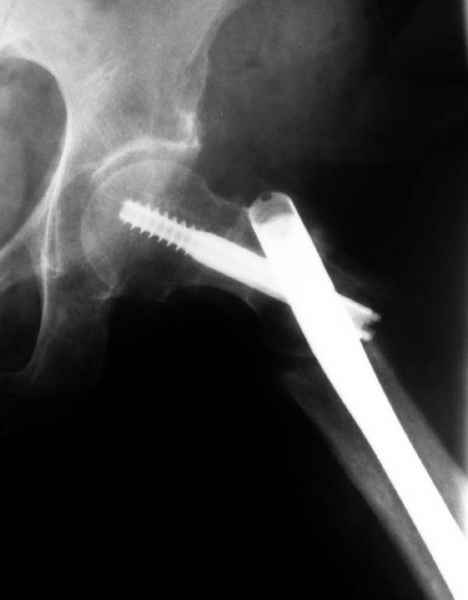

Не стали усложнять интрамедуллярным вариантом коррекции, легче контролировать коррекцию пластиной, поэтому сделали операцию 95 градусной Blade Plate, разогнув до 110 градусов.

Надеемся на успех, потому что до введения пластины дефект от импланта забили костной стружкой и удалось создать компрессию между отломками, максимальную для импланта (150 кило/паунд). Сделана дополнительная костная пластика и за счет измененного угла пластины устранено укорочение конечности.

Допущенные прежним врачом тактические и технические ошибок мы разобрали на нашей конференции по ошибкам "M&M".

Страйкер предоставил отличный инструмент - крючок для удаления длинного гвоздя. Считаем, что врачебная ошибка по установке привела к несостоятельности импланта и к ятрогенному осложнению.